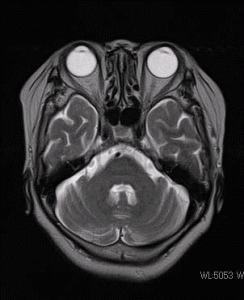

MRI(磁気共鳴画像装置)を導入致しました。

MRI検査により、今まで分からなかった脳の病変が、

簡単に見つけられるようになりました。

(頭部の断面画像)

画像提供:東芝メディカルシステムズ株式会社様